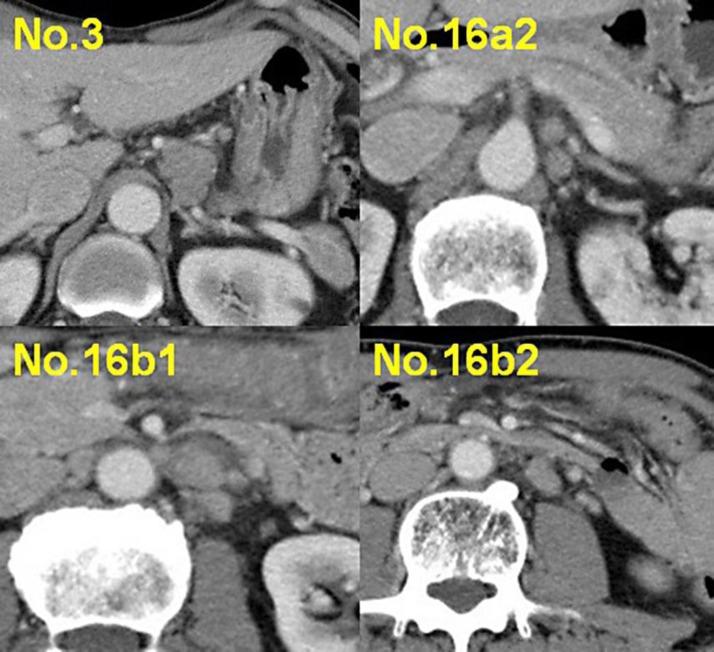

We report the case of a 60-year-old male who was diagnosed with gastric cancer. Upper gastrointestinal endoscopy indicated advanced cancer in the posterior wall of the gastric body. Biopsy revealed poorly differentiated adenocarcinoma. Abdominal computed tomography demonstrated thickening of the gastric wall and enlargement of the regional lymph nodes and of the para-aortic lymph nodes (PAN). The involvement of the PAN extended from the celiac axis to the caudal area of the inferior mesenteric artery [cT3N3aH0P0M1(LYM), stage IV]. Systemic chemotherapy was initiated. After 3 courses of S-1 plus cisplatin combination chemotherapy, the primary lesion and the enlarged lymph nodes revealed marked regression except for a minute residual lesion in the lymph nodes. Upon obtaining informed consent, open distal gastrectomy, D2 lymphadenectomy with PAN dissection, and Roux-en-Y reconstruction were performed. The patient was discharged from the hospital 35 days after the operation. Histopathological examination of the resected samples revealed malignant cells only in the PAN, not in the stomach or in the regional lymph nodes [ypT0N0M1(LYM), stage IV]. Currently, the patient is undergoing postoperative adjuvant chemotherapy with S-1 and has remained well without any recurrence after 6 months following surgery.

我们报告一例60岁男性胃癌患者。上消化道内镜检查显示胃体后壁为进展期癌。活检显示为低分化腺癌。腹部计算机断层扫描显示胃壁增厚,区域淋巴结及腹主动脉旁淋巴结(PAN)肿大。PAN受累范围从腹腔干延伸至肠系膜下动脉尾部区域[cT3N3aH0P0M1(LYM),IV期]。遂开始全身化疗。在进行3个疗程的S-1联合顺铂化疗后,除淋巴结有微小残留病灶外,原发灶及肿大淋巴结均显示明显消退。在获得知情同意后,实施了远端胃大部切除术、D2淋巴结清扫及PAN清扫,并进行了Roux-en-Y重建。患者术后35天出院。切除标本的组织病理学检查显示,仅在PAN中有恶性细胞,胃及区域淋巴结未见恶性细胞[ypT0N0M1(LYM),IV期]。目前,患者正在接受S-1辅助化疗,术后6个月无任何复发,情况良好。